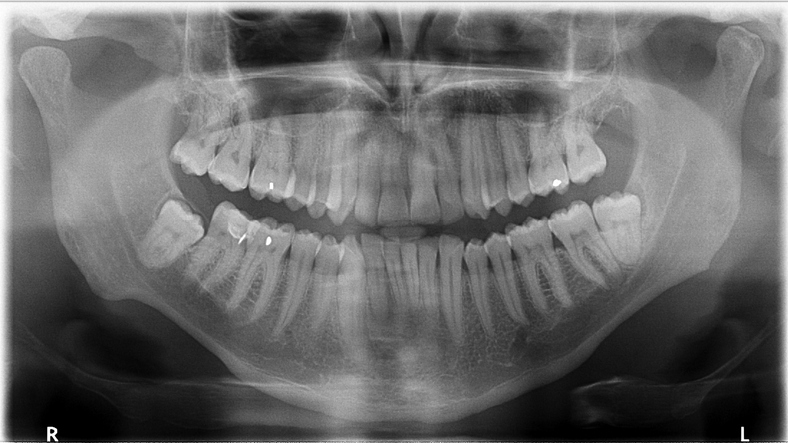

19.“My cavities don’t ever show up on X-rays. Dentists don’t believe me, even ones that have experienced it with me prior. I end up with an infection and a root canal every time.”